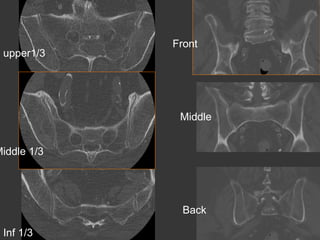

•  Female 58 years buttock pain with inflammatory

rhythm

Osteoarthritis

•

Multiple pregnancies.. Elderly… Weight

Location middle 1/3 , anterior

Common - Bilateral asymmetric - Spurs

Check the pubic symphysis

upper1/3

Front

Middle

Middle 1/3

Back

Inf 1/3